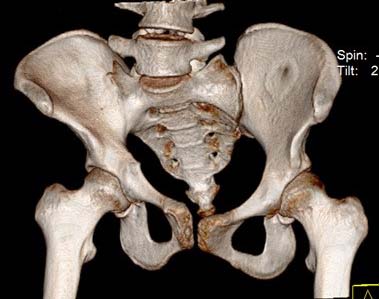

Здравствуйте.Помогите с диагнозом и тактикой лечения.

Больная 15 лет. Жалобы: на укорочение правой нижней конечности, хромоту. Анамнез: Со слов

болеет с детства, травму отрицает. Ранее за медицинской помощью не обращалась. Последние 2

года отмечает резкое укорочение конечности. Локально: При осмотре отмечается умеренное

искривление позвоночника во фронтальной плоскости, умеренная асимметрия лопаток и

надплечий. Скошенность таза. Отмечается укорочение правой нижней конечности на 3 см.

Движения в тазобедренном и коленном суставах в полном объеме. Нейрососудистых нарушений в

периферических отделах нет.